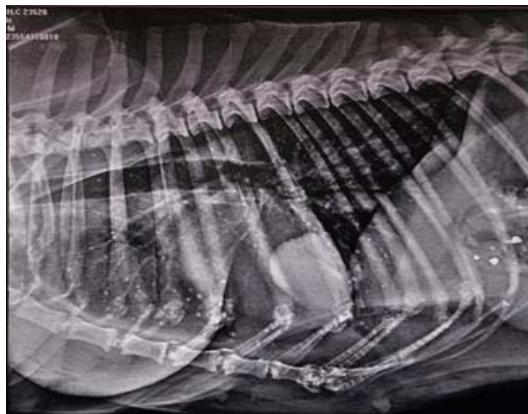

Fig. 7: Skiagram of the thorax showing pulmonary miliary nodules, pulmonary micronodules at the cranioventral region and pulmonary mass at caudoventral region of lung parenchyma and suspecting cavitation at the cranioventral area in right lateral view in dog Ag